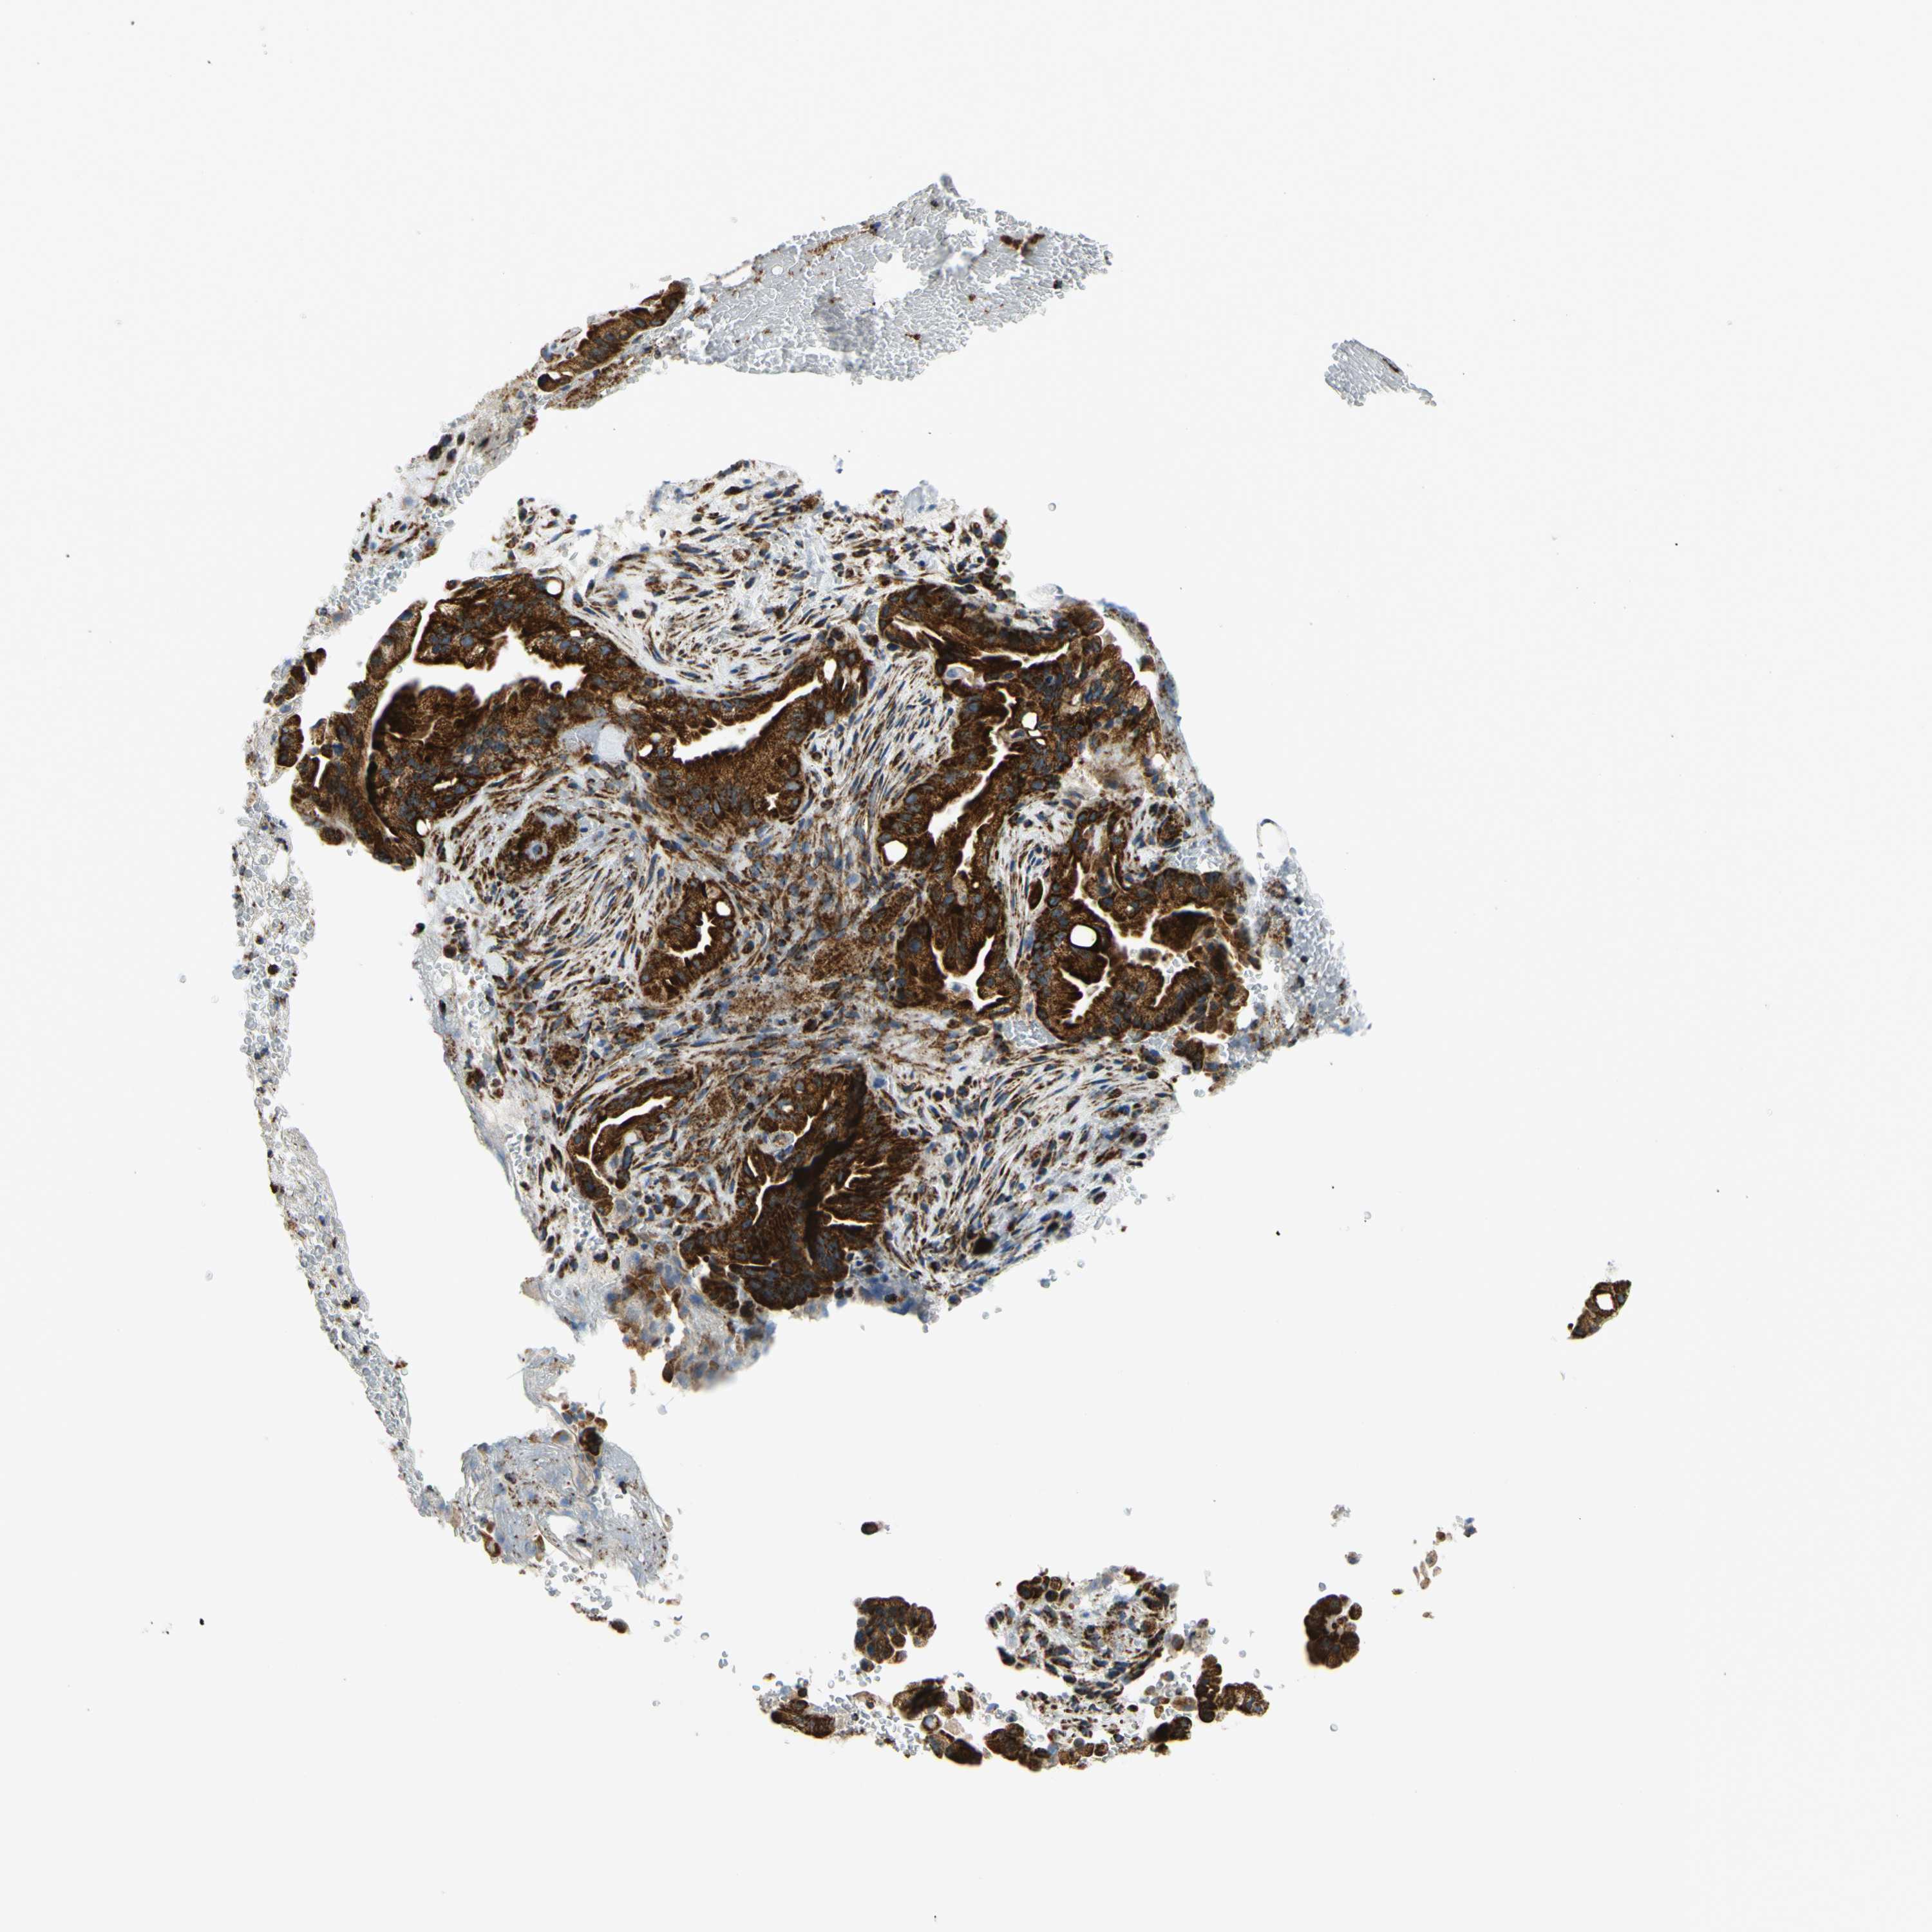

LIVER CANCER - Protein expressioni

A mouse-over function shows sample information and annotation data. Click on an image to view it in a full screen mode. Samples can be filtered based on level of antibody staining by selecting one or several of the following categories: high, medium, low and not detected. The assay and annotation is described here.

Note that samples used for immunohistochemistry by the Human Protein Atlas do not correspond to samples in the TCGA dataset.

Antibody stainingi

Antibody staining in the annotated cell types in the current human tissue is reported as not detected, low, medium, or high, based on conventional immunohistochemistry profiling in selected tissues. This score is based on the combination of the staining intensity and fraction of stained cells.

Each image is clickable and will lead to virtual microscopy that enables deeper exploration of all samples and also displays staining intensity scores, fraction scores and subcellular localization as well as patient and tissue information for each sample.

Antibody HPA049850

Antibody HPA053524

Antibody CAB009187

Staining

High

Medium

Low

Not detected

Intensity

Strong

Moderate

Weak

Negative

Quantity

>75%

75%-25%

<25%

None

Location

Nuclear

Cytoplasmic/membranous

Cytoplasmic/membranous,nuclear

Carcinoma, Hepatocellular, NOS